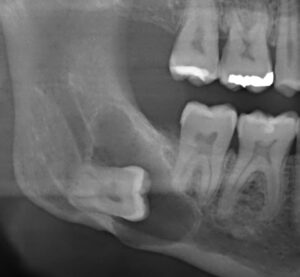

Weisheitszähne können Infektionen verursachen – Die erste Abbildung zeigt einen Weisheitszahn (schwarzer Pfeil), der aufgrund von Platzmangel nicht vollständig in die Mundhöhle ragt. Auf der zweiten Abbildung sieht man diesen Weisheitszahn (schwarzer Pfeil), der teilweise noch mit Schleimhaut bedeckt ist. Die dadurch entstehende „Zahnfleischtasche“ bildet ein Reservoir für Bakterien und kann Entzündungen begünstigen. Es empfiehlt sich deshalb, solche Zähne zu entfernen.